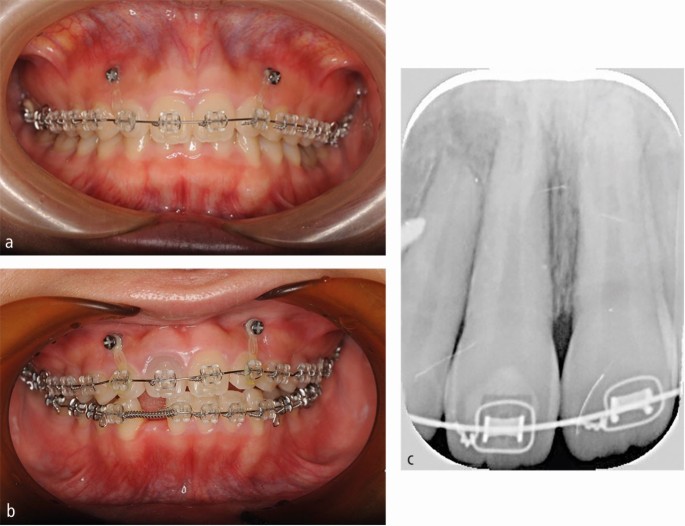

For orthodontic treatment, 0.018-inch standard edgewise brackets were bonded on the maxillary teeth. Two self-drilling TADs (diameter, 1.6 mm; length, 8 mm; Dual Top Auto Screw; Jeil Medical Corp, South Korea) were inserted into the buccal alveolar bone between the maxillary lateral incisors and canines to intrude the maxillary anterior teeth using an elastic chain. Before completion of opening the bite, positive crown torque of the upper incisors was achieved by torque moment generated with intruded force (Fig. 2A). After opening the bite, brackets were bonded on the mandibular teeth to create space between mandibular right central incisor and canine. However, after 12 months of intrusion, the crown of the maxillary right central incisor showed grey discoloration and a negative response to electric pulp tests (Fig. 2B). Furthermore, the patient reported severe spontaneous pain only in this tooth two days before visiting our clinic. However, no significant radiographic change was observed around the root apex of the maxillary right central incisor. Notably, moderate apical root resorption was observed in the maxillary right lateral incisor by the dental x-ray (Fig. 2C). From these symptoms, we thought traumatic pulp injury occurred on the right central incisor. Therefore, we removed the orthodontic force on the maxillary incisors with passive wire ligations between TADs and the upper canines, and 60 mg of loxoprofen sodium was administered three times a day for seven days. No more intrusion force to the upper incisors was applied because opening the bite had been completed. Six months after stopping orthodontic treatment, resolution of the crown discoloration was observed and the response to electric pulp testing was restored (Fig. 3A). Periapical radiography revealed a distinct radiolucency at the root apex (Fig. 3B). Two years after initiation of orthodontic treatment, the patient's gummy smile and overbite were corrected with a good intercuspal relationship. The missing mandibular right lateral incisor was replaced by direct bonding (Fig. 4A, Fig. 4B). Follow-up at four years after beginning of retention revealed stable smile aesthetics and tooth positions (Fig. 4C, Fig. 4D). Periapical radiographs showed marked root canal obliteration in the maxillary right central incisor and remodelling of the root apex in the maxillary right lateral incisor (Fig. 4E). The wire sequence used in this case is shown in Table 1.

Studies describing TAB during orthodontic treatment are scarce,9 and the mechanism of TAB is not completely clarified. However, orthodontic tooth movement likely induces non-infectious inflammation of the apical pulp tissue. McDonald reported that continuous orthodontic tipping forces caused a decrease in the pulpal blood flow.1 Miura showed that pulp necrosis occurred under continuous heavy orthodontic forces due to rupture of blood vessels in the root apex.2 Moreover, the pulp tissue in the root apex plays an essential role in the incidence of inflammatory periapical root resorption during orthodontic tooth movement.10 Tsukiboshi suggested the following mechanism for TAB.11 Immediately after trauma, the apical blood vessels rupture, and ischemic pulp necrosis is induced. Next, pulp necrosis causes non-infectious inflammation in the apical pulp tissue with periapical alveolar bone and root resorption. Several months after trauma, the foramen of the root apex expands because of inflammatory apical root resorption, followed by recovery of the periapical blood vessels. Finally, the pulp tissue shows obliteration several years after trauma. This sequence of pulp healing was distinctly observed in our patient. Interestingly, TAB in the maxillary right central incisor and mild apical root resorption in the maxillary right lateral incisor occurred spontaneously in our patient. These findings strongly suggested that both TAB and apical root resorption during orthodontic tooth movement are caused by the same inflammatory periapical reaction. Similar inflammatory reactions were observed in the root apex during orthodontic tooth movement in animal studies. Yamamoto showed that the expression of interleukin-1β, receptor activator of nuclear factor kappa-B ligand, tumour necrosis factor-α, and macrophage colony-stimulating factor in the apical pulp tissue increased after orthodontic tooth movement in rats.8 Interestingly, these inflammatory reactions decreased with loxoprofen or acetaminophen administration.8,12 Ersahan reported that pulpal blood flow decrease during orthodontic tooth movement in older patients was more severe and persisted for a longer duration than that in younger patients.13 Similarly, Andreasen reported that TAB is more likely to occur in patients aged <20 years.5 Considering these findings, we prescribed 60 mg of loxoprofen sodium three times a day for seven days and removed the orthodontic force immediately after the appearance of crown discoloration in the maxillary right central incisor to improve TAB. Consequently, the crown colour improved and sensitivity to electric pulp testing returned after six months. The findings in this case suggest that removal of orthodontic force is the first-line treatment to improve TAB during orthodontic treatment, and NSAIDs may help improve non-infectious pulpal inflammation, even in older patients.